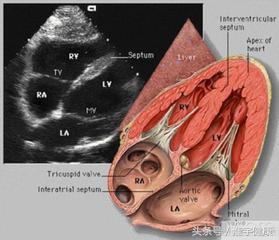

三、心室彩超

心室彩超是唯一能动态显示心腔内结构、心室的搏动和血液流动的仪器,对人体没有任何损伤。心室探头就像摄像机的镜头,随着探头的转动,心室的各个结构清晰地显示在屏幕上。

主要检查心室的形态学有没有什么异常,以及心功能是否正常,特别对先天性心室病是首选的检查方法

心室彩超显示的是心室的内部结构异常,房室大小的变化以及血流的速度和方向,在心室病的诊断中具有重要的价值.一般心情,睡眠对检查的结果有一定的影响,建议您避免紧张情绪,按时休息即可。